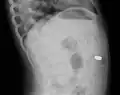

Lateral X ray showing a 9mm battery in the intestines -